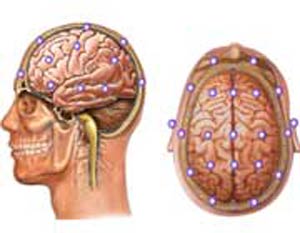

مغز